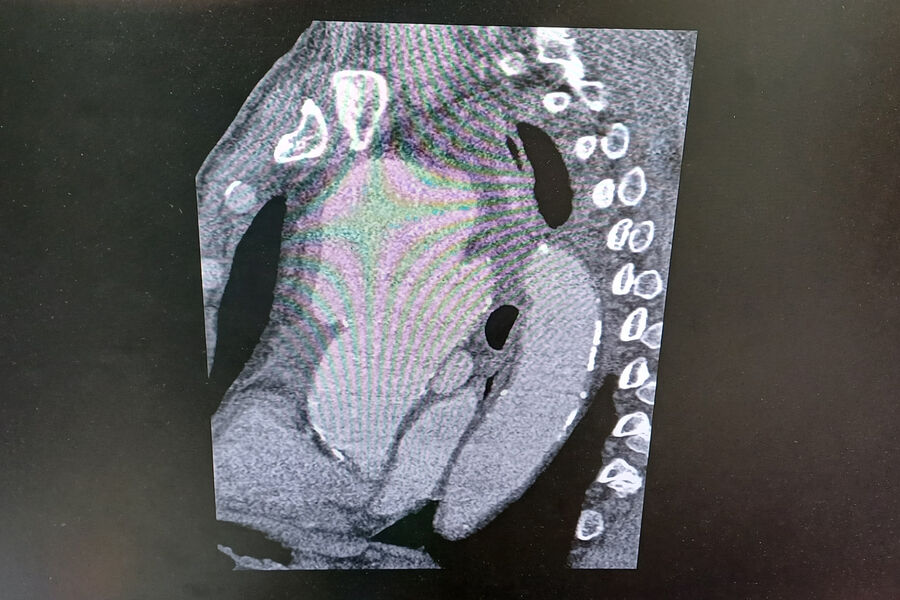

«Компьютерная томограмма подтвердила выпячивание аорты размером 9 на 9 сантиметров. Гигантская мешотчатая аневризма, больше, чем гусиное яйцо», — рассказал заведующий отделением №5 Рязанского кардиодиспансера Сергей Загородний.

По словам специалиста, аневризма сдавливала все близлежащие органы и ткани: трахеи, бронхи, верхнюю полую вену.